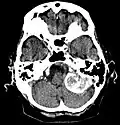

Kontrastmittel aufnehmendes Meningeom der linken Hemisphäre in der Computertomographie -

Großes Felsenbeinmeningeom in der Computertomographie -